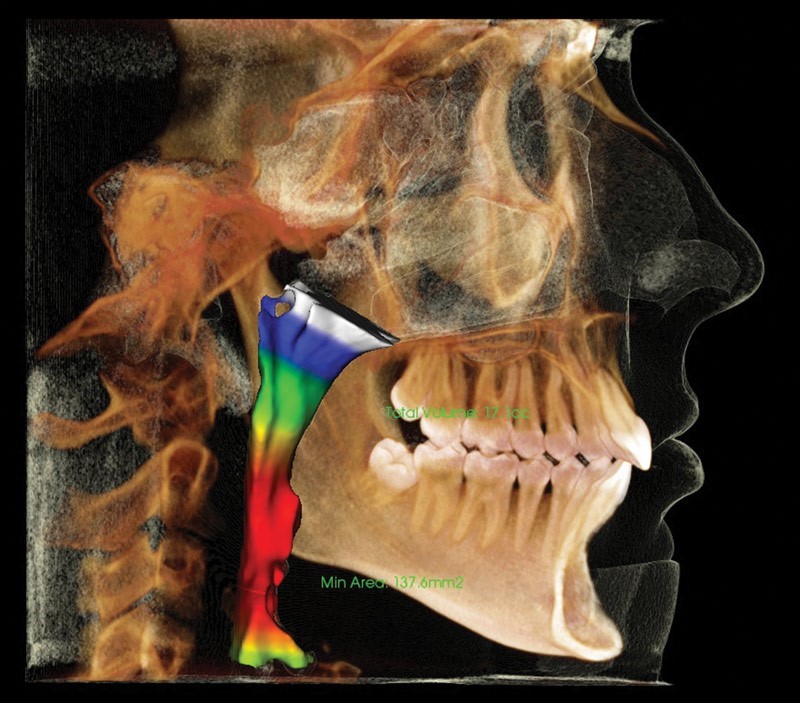

6. Đánh giá đường thở trên phim CBCT

Một bệnh nhân có triệu chứng ngáy hay khó thở về đêm có thể do nguyên nhân bị hẹp đường thở, việc dùng CBCT và phần mềm phân tích đường thở có thể chẩn đoán những vùng khí quản bị hẹp bất thường dẫn đến lưu lượng khí đi qua đó giảm, hoặc tiên đoán trước những trường hợp khó thở, từ đó có thể chỉ định điều trị chỉnh nha hoặc đeo khí cụ chống ngày phù hợp.

Phân tích đường thở với biểu đồ lưu lượng khí (đa màu) trên phim CBCT